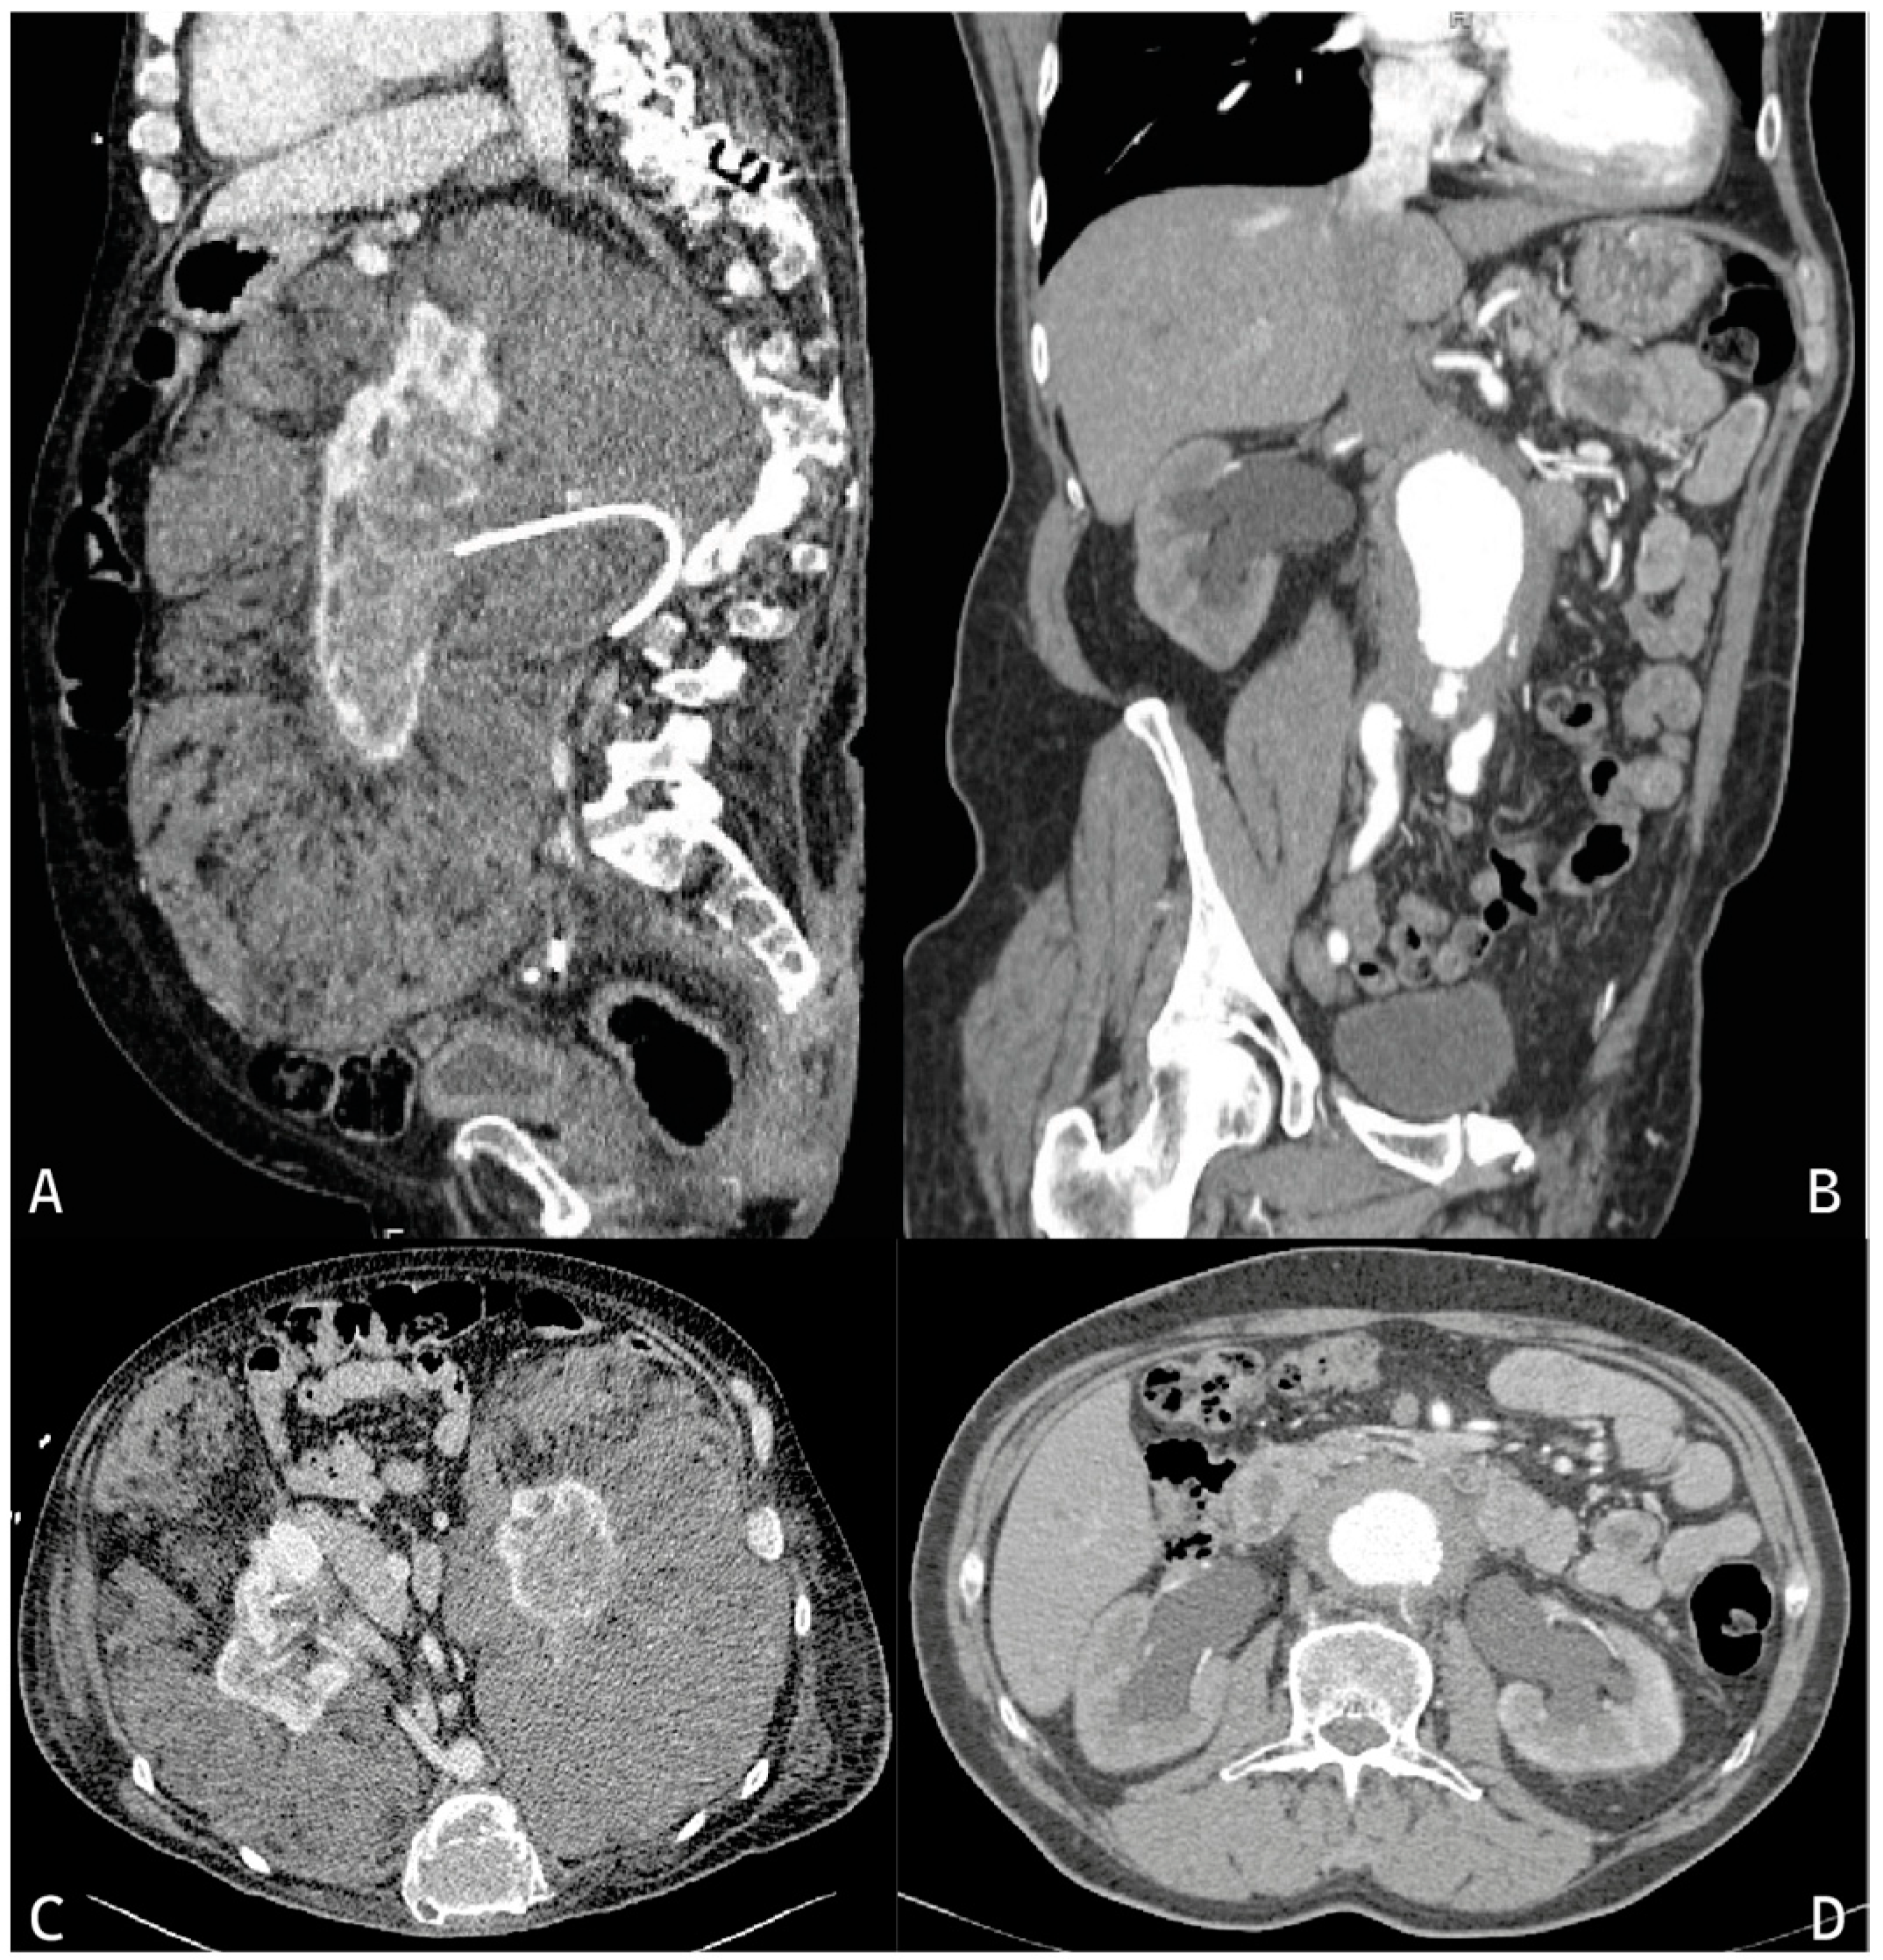

- Wu, Z.; Jiang, G.L.; Tang, Y.; Jiang, C.; Sun, L.L.; Li, N.; Jin, Z.Y.; Sun, H. Urinary involvement in Erdheim-Chester disease: Computed tomography imaging findings. Abdom. Radiol. 2021, 46, 4324–4331. [Google Scholar] [CrossRef]